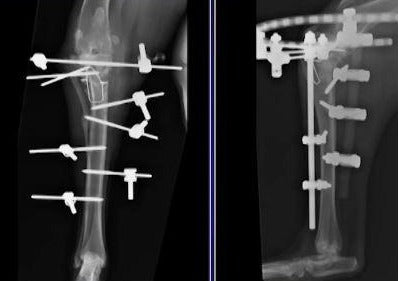

Cranial cruciate ligament insufficiency is the most common cause of lameness necessitating surgery in dogs. The resultant instability produces degenerative joint disease and can result in meniscal trauma. Surgery is often advocated to improve limb function and there are a number of surgical procedures that have been described to manage dogs with this condition. This session will focus on the current state of surgical management of dogs with cranial cruciate ligament insufficiency.

Supported by Veterinary Orthopedic Implants